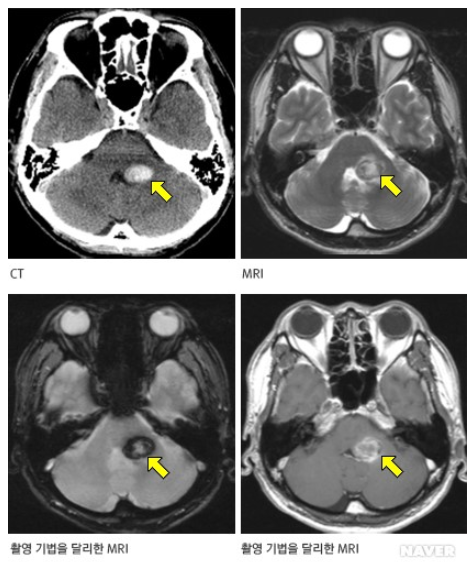

해면상혈관종은 뇌, 척수에서 모세혈관이 비정상적으로 팽창해 해면체 모양으로 뭉쳐진 종괴다. 시간에 따라 병변의 수가 증가하고 다발성 뇌출혈을 유발할 수도 있어 주의가 필요하다.

그 중 상염색체 우성으로 유전되는 ‘가족성’ 해면상혈관종은 유전자변이 3가지(KRIT1, CCM2, PDCD10)에 의해 발생한다고 알려졌다. 그러나 세계적으로 이 질환의 유전자변이 별 특성에 대한 연구가 부족한 실정이었다.

추가로 연구팀이 가족성 해면상혈관종의 발생 부위를 분석한 결과, 유전자변이 보유 환자는 ‘뇌간’ 부위에 병변이 발생하는 빈도가 확연히 높은 것으로 확인됐다. 즉, MRI 검사 시 뇌간 부위에서 해면상혈관종이 발견된 사람은 유전자변이 보유 가능성이 있으므로 특히 유전자검사를 권고한다고 연구팀은 강조했다.